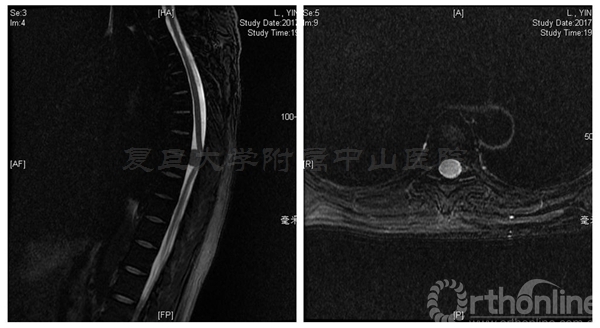

术前MRI:T7-8水平椎管内占位伴脊髓变性,脊膜瘤可能的大

术后半年CT显示两侧椎板截骨面均已骨性愈合,椎管体积无减少。MRI显示椎管内脊膜瘤无复发